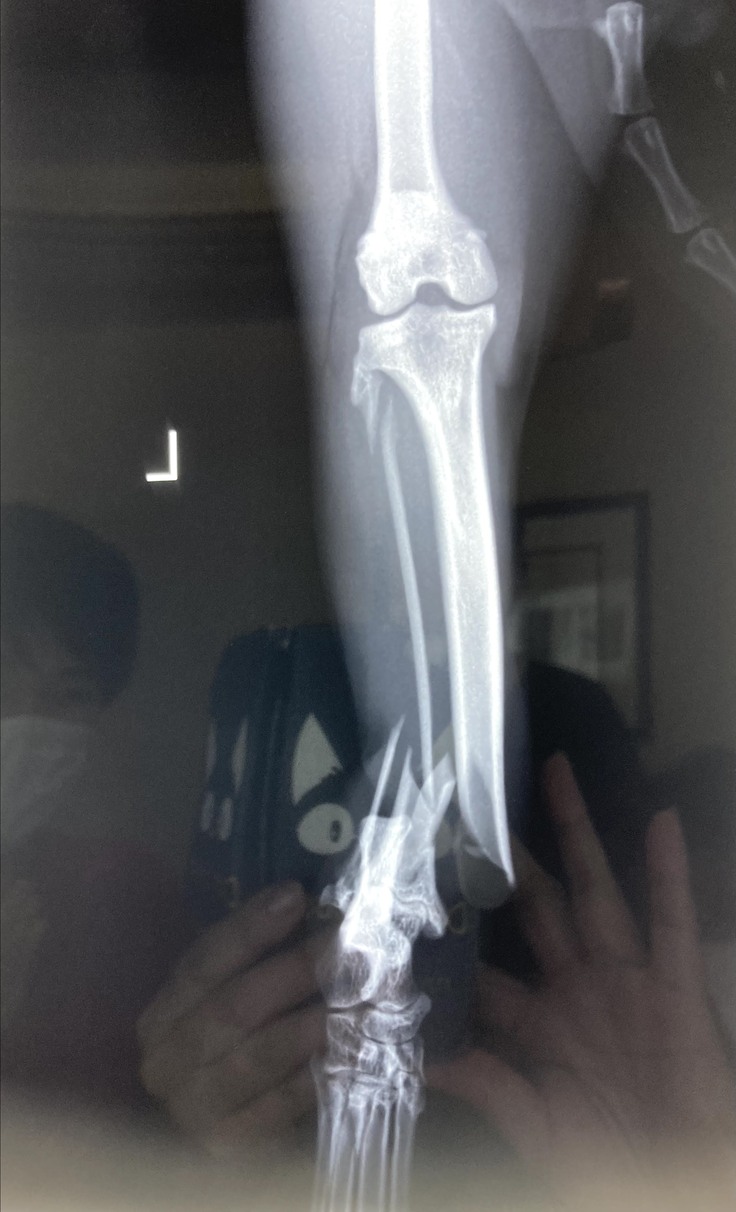

今回このくーちゃんが左後ろ足を開放性剝離骨折してしまいました。骨が3分割と小さな骨に分かれてしまっていてプレートを入れ小さい骨はピンで止めていただき手術は大成功しました。しかし創部に感染があった為術後も入院が長引きました。退院して2日後又発熱しぐったりし受診、感染からの熱か再入院。その退院の2日後にまた患部が凄く熱くぐったりし受診。今回は手術の部位が再度骨折してしまっていました。毎日ケージの中でほぼほぼ寝たきりであったのですが何故か再度骨折。かなり痛みもある様で可哀想に熱もでていました。私は死んでしまうのではと夜中に何度も見に行く日々が続きました。

悲しいことに手術してもらった所が再度骨折。

上が7月10日、下が15日 真ん中の小さい骨がずれてピンが横を向いてしまっています。